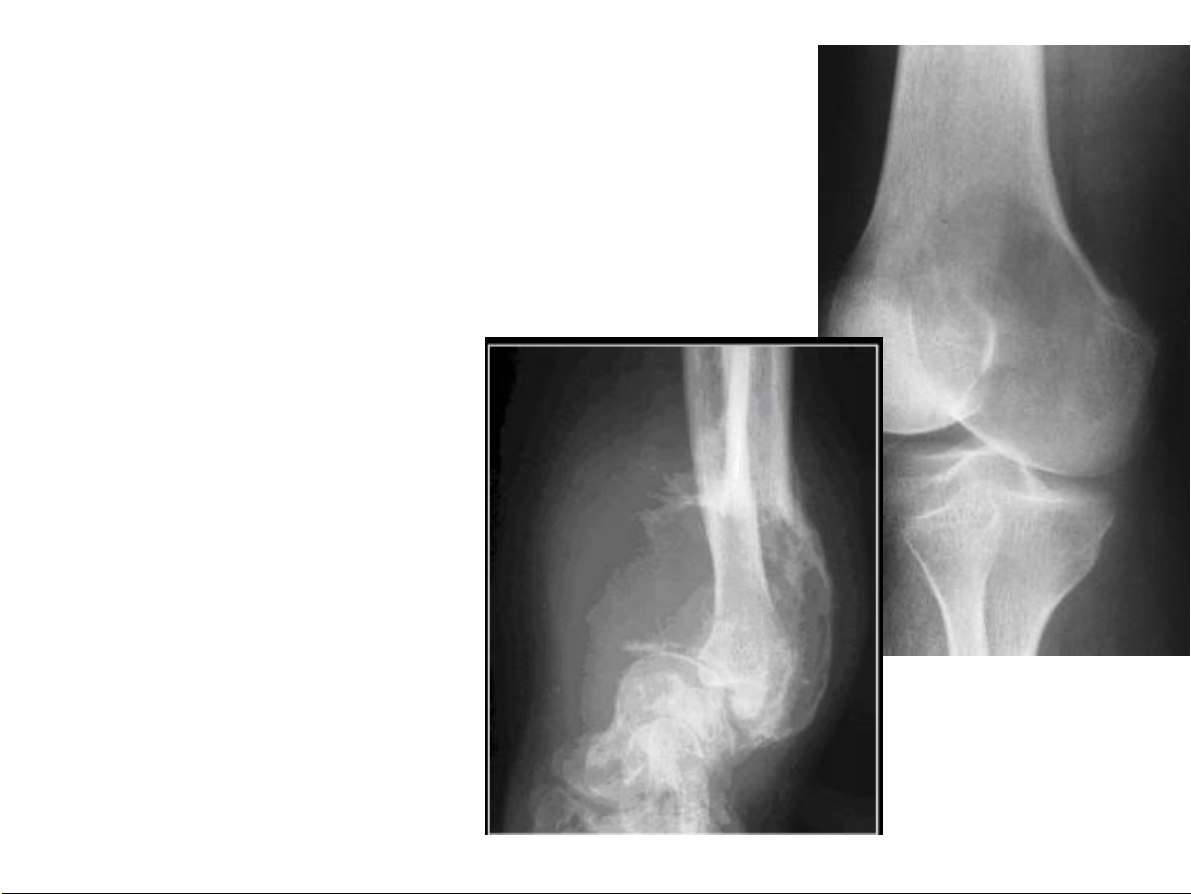

Bất thường về cấu trúc Tạo xương: phản ứng tân tạo xương 31-Jan-23 CĐHA Cơ-Xương-Khớp